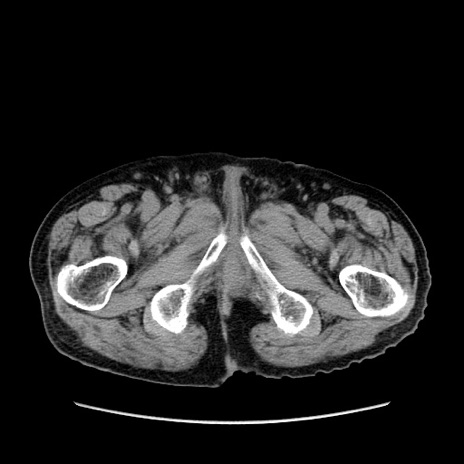

症例24(横断像)

【症例】80歳代男性

【主訴】左側腹部痛、嘔吐

【現病歴】本日早朝より左腹部に痛みあり。昼頃嘔吐認めたため、救急要請。

【既往歴】直腸癌(Mile手術)、胆摘

【身体所見】意識清明、BT 35.9℃、BP 221/93mmHg、SpO2 97%(RA) 、腹部:左ストーマ周囲に限局性の腹部膨隆あり。 膨隆部自発痛・圧痛あり・軟。

【データ】WBC 7700、CRP 0.09